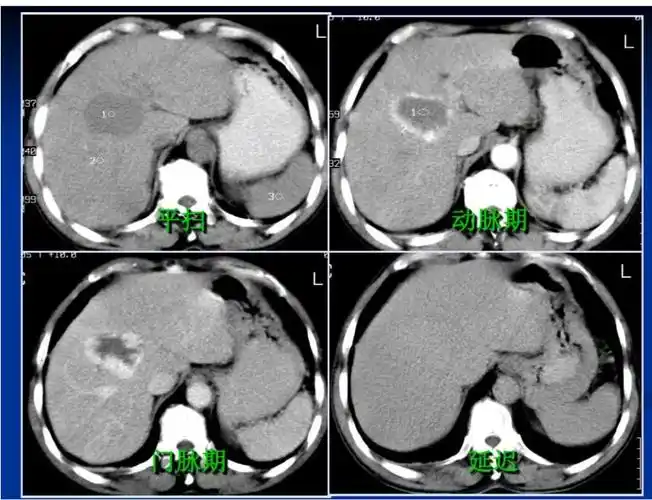

肝血管瘤ct表现

肝脏血管瘤影像学表现及鉴别诊断二影像天地

肝脏血管瘤影像学表现及鉴别诊断(一) | 影像天地

肝脏丨血管瘤